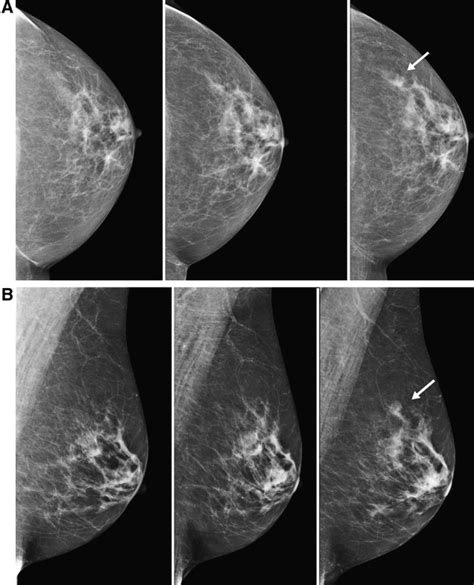

To tackle the complexities of overlapping breast lesions , radiologists rely on a sophisticated arsenal of imaging techniques. The first line of defense is often mammography , the standard screening tool. While it provides a 2D view, different projections (like craniocaudal and mediolateral oblique) can help shift the breast tissue and potentially separate overlapping structures. However, as we’ve discussed, dense tissue and true overlap can still pose challenges. This is where digital breast tomosynthesis (DBT) , often called 3D mammography, shines. DBT takes multiple low-dose X-ray images from different angles and reconstructs them into thin slices of the breast. This slicing effect is revolutionary because it allows the radiologist to scroll through the breast tissue, layer by layer, significantly improving the ability to distinguish overlapping lesions and detect abnormalities that might be hidden in a standard 2D mammogram. It’s like being able to see individual pages in a book rather than just a flat cover. Breast ultrasound is another critical tool. It uses sound waves to create images and is excellent at differentiating solid masses from fluid-filled cysts. When lesions overlap on a mammogram, ultrasound can often provide a clearer picture of their individual characteristics, especially if one is cystic and the other solid. It can also help guide biopsies with great precision. For particularly challenging cases, or when mammography and ultrasound are inconclusive, Magnetic Resonance Imaging (MRI) of the breast is often employed. MRI uses magnetic fields and radio waves to generate highly detailed images. It offers superior soft-tissue contrast and can often visualize and delineate separate lesions, even when they are closely situated. Contrast-enhanced MRI is particularly valuable as it can highlight areas of abnormal blood supply, which is common in malignant tumors. The choice of imaging technique often depends on the initial findings, the patient’s risk factors, breast density, and the specific questions that need to be answered. Combining the strengths of these different modalities is key to accurately diagnosing and managing overlapping breast lesions , ensuring that no abnormality is missed and that patients receive the most appropriate care. These advanced techniques are vital for untangling these complex presentations and providing peace of mind.